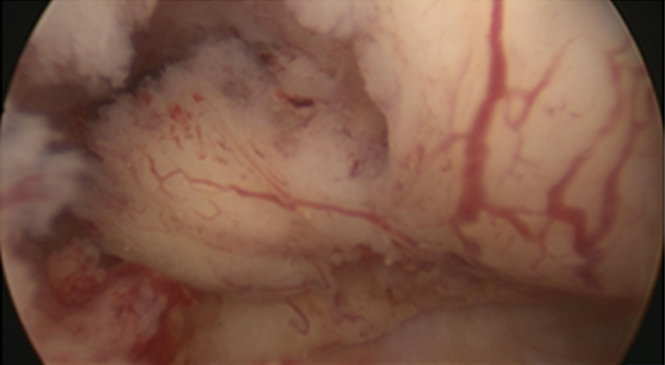

Vous réalisez une hystéroscopie qui retrouve ceci : Figure 1 (Source : Pr Agostini, hôpital de la Conception, La Revue du Praticien)

Question 12 - Quel diagnostic évoquez-vous en priorité ?

La lésion intracavitaire est irrégulière, vascularisée ; un cancer de l’endomètre est à évoquer en priorité.

Le fibrome sous-séreux est par définition visible à l’extérieur de la cavité, au cours d’une cœlioscopie, par exemple.

L’hyperplasie endométriale se présente de façon plus diffuse.

L’anatomopathologiste conclut à un adénocarcinome endométrioïde utérin de grade I.